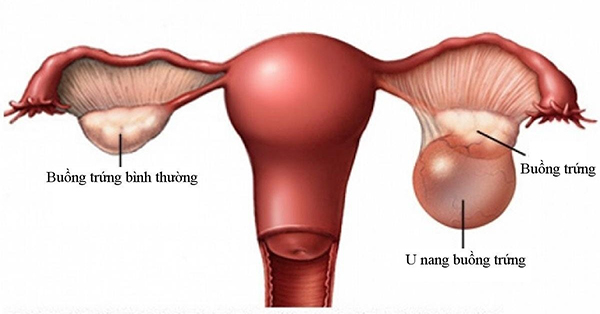

U nang buồng trứng là loại bệnh khá phổ biến ở phụ nữ, đặc biệt là những người đang trong độ tuổi sinh đẻ. Các số liệu thống kê cho thấy, U nang buồng trứng chiếm khoảng 3.6% các bệnh phụ khoa thường gặp.

Các dấu hiệu thường gặp giúp nhận biết sớm bệnh u nang buồng trứng

Xuất hiện những cơn đau bất thường: Những cơn đau bất thường bao gồm đau rát khi quan hệ, đau đớn dữ dội khi đến chu kỳ hành kinh. Đau vùng xương chậu theo cơn hoặc trong một thời gian dài. Thường xuyên đau tức bụng do khối u chèn ép, cảm giác vùng bụng có vật chướng đang phát triển.

Kinh nguyệt mất đều đặn, chu kỳ thất thường: Khi kinh nguyệt hàng tháng của bạn không đều đặn. Mỗi lần đến tháng đều đau bụng nhiều, ra nhiều máu đen, khí hư có mùi thì đây cũng là một trong những triệu chứng của U nang buồng trứng

Đi tiểu nhiều, tiểu dắt: Việc buồng trứng xuất hiện u, ở 1 kích thước đủ lớn sẽ gây chèn ép bàng quang gây ra hiện tượng: tiểu nhiều, tiểu dắt.

Đây là những biểu hiện sát nhất của bệnh U nang buồng trứng. Khi có biểu hiện này bạn nên đi khám. Bác sĩ sẽ giúp bạn tiến hành thăm khám và siêu âm.